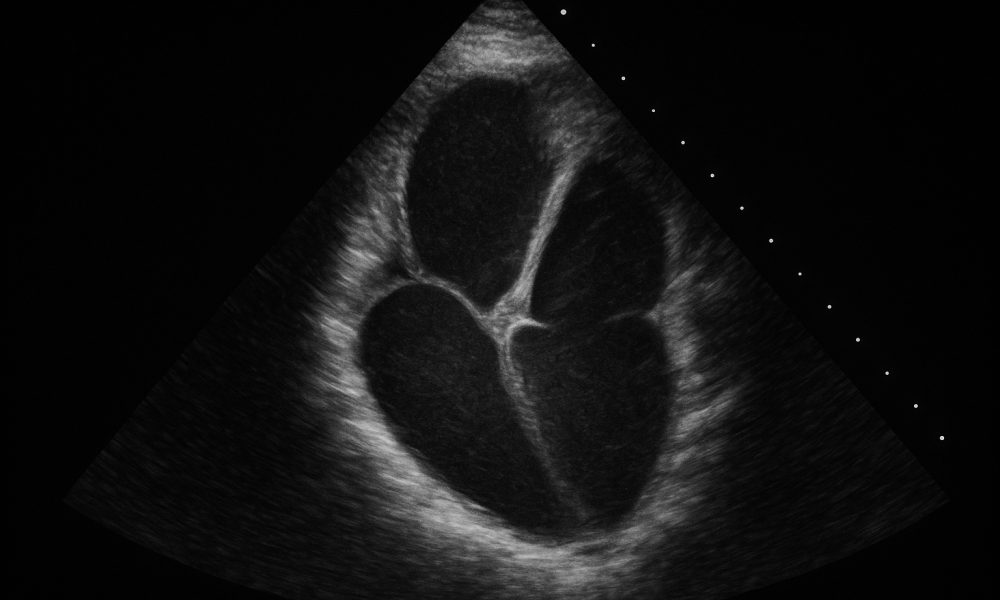

A non-invasive heart scan helped confirm the impact of my Don’t Die prevention plan and set a new baseline for long-term cardiovascular health. Today, I want...